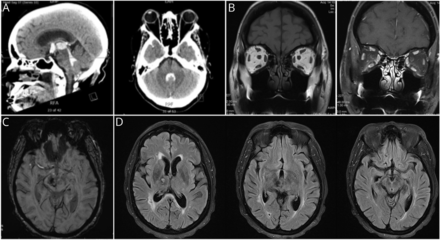

高血压史的一个51岁的女人面对左虚弱和复视。成像显示一个大出血性梗塞涉及右侧丘脑和吻侧中脑与脑室扩展(图)。Neuro-ophthalmic检查证明与限制的双边upgaze麻痹infraduction右边(视频1),克服了娃娃的头操作(视频2)。双边盖子收缩有显著降低收敛以及convergence-retraction眼球震颤。垂直的和一个一半综合征是一种罕见的表现造成单方面thalamomesencephalic中风与参与的间质核吻侧内侧纵束和后连合1在这里伴着背中脑综合症。

图

对thalamomesencephalic中风导致垂直半综合症

(一)矢状轴向(右)(左)和CT图像显示急性脑室,intrathalamic和中脑的出血。(B) MRI冠状切片显示正常的轨道(左:t1,右:t1脂肪饱和postcontrast)。(C) Susceptibility-weighted轴切片显示含铁血黄素沉积和(D) t2加权fluid-attenuated反转恢复图像显示体积丧失正确的丘脑和中脑个月后严重的侮辱。